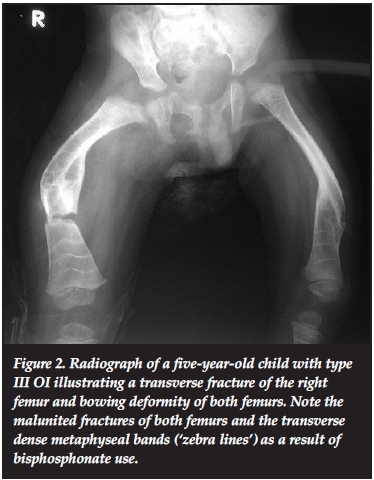

Most of the patients in our series presented with the typical features of OI. These included blue sclerae in 52.6% (41 patients). Figure 1 illustrates blue sclera in a two-year-old female child with type III OI. Dentinogenesis imperfecta was seen in 26.7% (21 patients). Triangular facies were seen in 50.0% (39 patients). The other features included recurrent fractures (Figure 2) and lower limb deformities in 66.7% (52 patients).

The patients were classified clinically using the original Sillence classification, and the number and percentages of each type of OI are shown in Table I. The majority of patients in this study were classified as type III and type IV: 38 (48.7%) and 23 (29.5%) patients respectively. Thus, the more severe types of OI were seen at the Metabolic Bone Clinic. There were no patients with type II OI as the patients were collected from the Metabolic Bone Clinic and did not include patient records of those seen as inpatients in the neonatal wards.